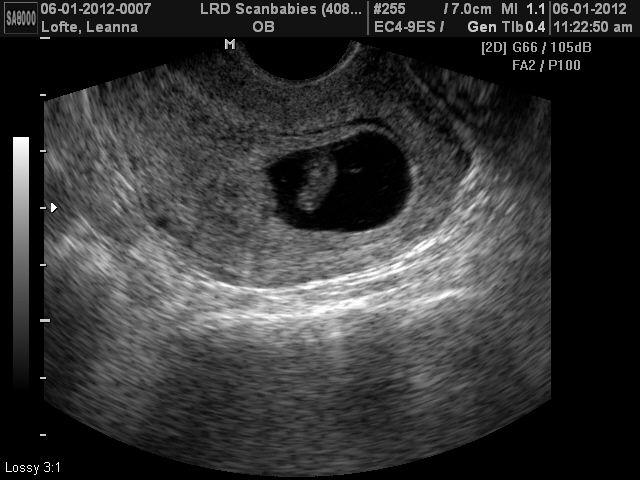

Ниже представлены фото УЗИ плода на седьмой неделе беременности:

На седьмой неделе беременности многие женщины впервые посещают врача для проведения ультразвукового исследования (УЗИ). Это важный этап, который позволяет не только подтвердить факт беременности, но и оценить состояние плода и здоровье матери.

Первое УЗИ обычно проводится в период с 6 по 8 неделю беременности. На этом этапе врач сможет увидеть эмбрион и его сердцебиение, что является важным показателем нормального развития. Во время процедуры используется специальный датчик, который излучает ультразвуковые волны, отражающиеся от тканей и создающие изображение на экране.

- Размеры эмбриона: На седьмой неделе эмбрион обычно достигает длины около 1-2 см. Врач измерит его размеры, чтобы убедиться, что они соответствуют сроку беременности.

- Сердцебиение: Одним из самых волнующих моментов является возможность услышать сердцебиение эмбриона. Это свидетельствует о том, что он развивается и получает необходимое количество кислорода.

- Количество эмбрионов: УЗИ также позволяет определить, сколько эмбрионов развивается в матке. Это важно для женщин, которые прошли процедуру ЭКО или имеют в анамнезе многоплодную беременность.

- Состояние матки: Врач оценит состояние матки и яичников, чтобы исключить возможные осложнения, такие как внематочная беременность или кисты.